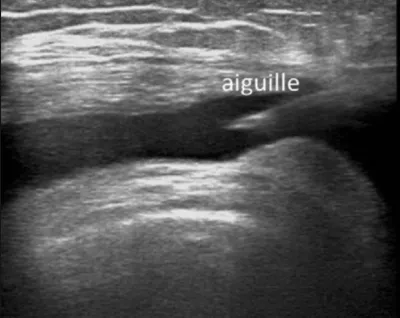

L'injection d'un corticoïde dans une articulation, au niveau d'une bourse de glissement ou au contact d'un tendon est communément appelée "infiltration".Nous réalisons ce geste avec un guidage échographique afin d'injecter au mieux le médicament cortisonique.L'infiltration peut être couplée avec u...

Une ponction à l'aiguille d'un épanchement, d'un hématome ou d'un kyste poplitée est possible avec un guidage échographie. le guidage échographique permettra de localiser en temps réel l'aiguille.Une nettoyage soigneux de la peau sera réalisé au préalable. Ce geste est rapide, environ 5 minutes, e...